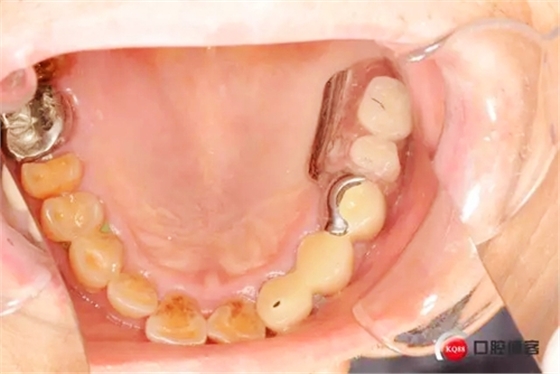

患者初診口腔情況15號(hào)牙為原做可摘局部義齒做卡環(huán)預(yù)備,真“專家”的活

1498573426_589043.jpg

23 24 殘根是為“專家”做的固定義齒2帶3的固定橋造成的后果,“磚家”厲害啊